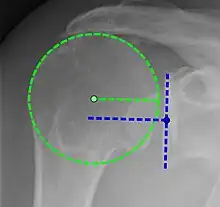

Xray

X-ray projectional radiography cannot directly reveal tears of the rotator cuff, a 'soft tissue', and consequently, normal X-rays cannot exclude a damaged cuff. However, indirect evidence of pathology may be seen in instances where one or more of the tendons have undergone degenerative calcification (calcific tendinitis). The humeral head may migrate upwards (high-riding humeral head) secondary to tears of the infraspinatus, or combined tears of the supraspinatus and infraspinatus.[47] The migration can be measured by the distance between:

- A line crossing the center of a line between the superior and inferior rims of the glenoid articular surface (blue in image).

- The center of a "best-fit" circle positioned over the humeral articular surface (green in image)

Normally, the former is positioned inferiorly to the latter, and a reversal is therefore indicating a rotator cuff tear.[47] Prolonged contact between a high-riding humeral head and the acromion above it, may lead to X-rays findings of wear on the humeral head and acromion and secondary degenerative arthritis of the glenohumeral joint (the ball and socket joint of the shoulder), called cuff arthropathy, may follow.[46] Incidental X-ray findings of bone spurs at the adjacent acromioclavicular joint may show a bone spur growing from the outer edge of the clavicle downwards towards the rotator cuff. Spurs may also be seen on the underside of the acromion, once thought to cause direct fraying of the rotator cuff from contact friction, a concept currently regarded as controversial.